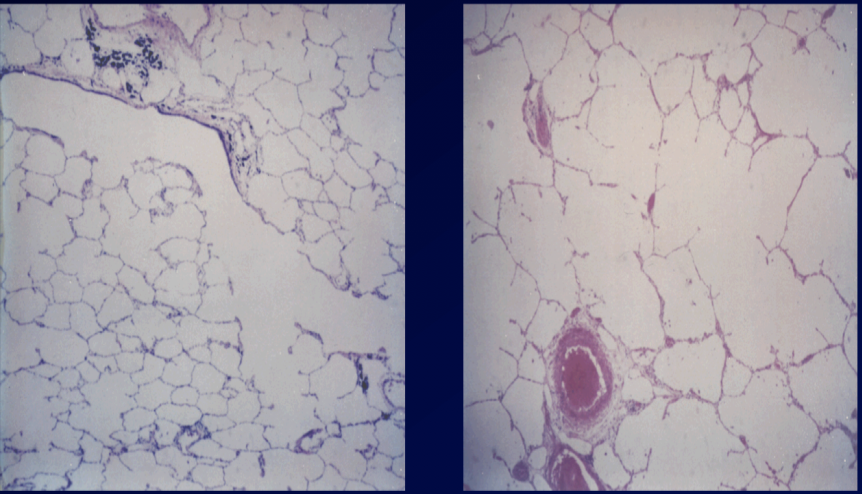

This pathology represents the ______ portion of COPD

This pathology represents the chronic bronchitis portion of COPD

This pathology represents the small airway remodeling portion of COPD